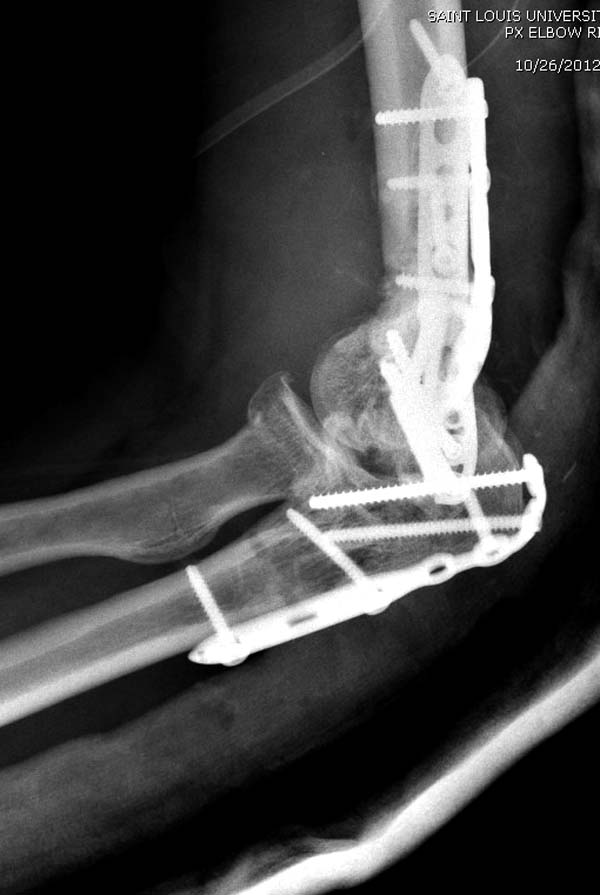

Примеры: первому более 15 лет фиксирован шурупом и tension band

technique, а второй перелом открытый больной 80 лет, после наружного

фиксатора в первом этапе и окончательная фиксация вторично. Третьий раз

внесуставная остеотомия...

Имя     : 2-1 Distal Humerus.jpg

Тип     : image/jpeg

Размер  : 66695 байтов

Описание: отсутствует

Url     : http://weborto.net:8080/pipermail/ortho/attachments/20130604/c45a379f/attachment-0020.jpg